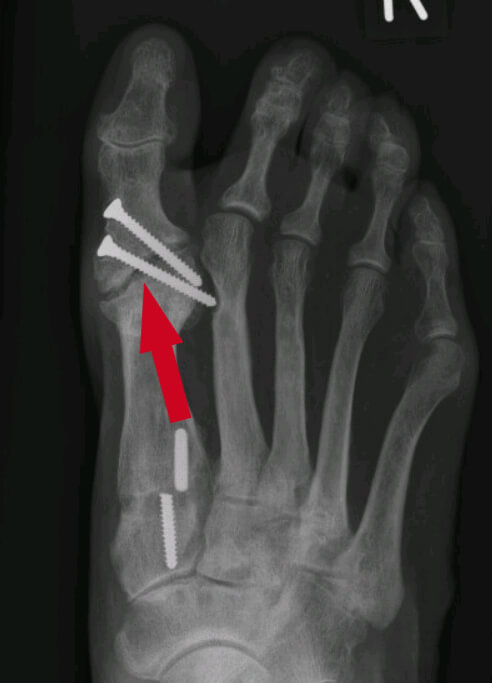

Uw specialist kan op een röntgenfoto zien of de botten goed aan elkaar zijn vastgegroeid.

Bij deze patiënt is het gewricht ondanks de schroeven niet vastgegroeid. De spleet (bij de pijl) had niet meer zichtbaar moeten zijn.